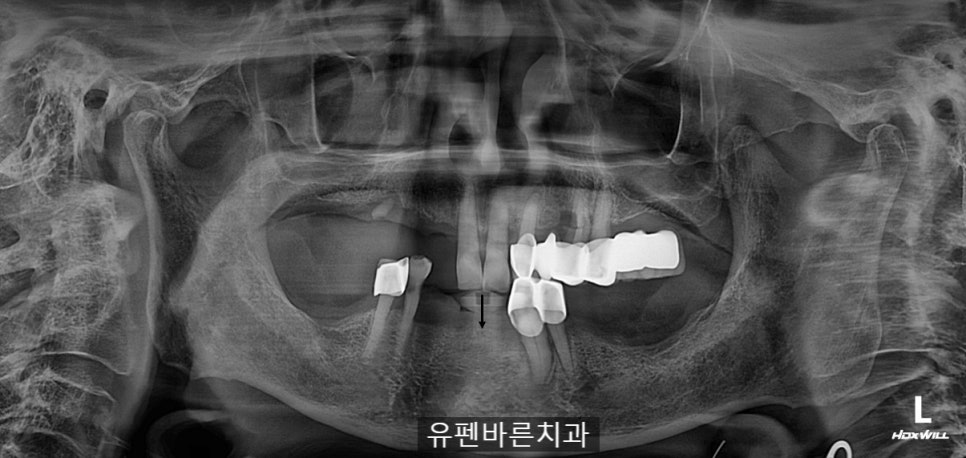

엑스레이 촬영 결과

교합이 맞지 않고,

왼쪽위의 브릿지는

흔들거리고

치아들이 정출되어

위 앞니가 내려와

아래 잇몸에 닿고 있는

상태셨어요,,,

남아있는 치아들 마저

보철물 안쪽으로

충치가 심해

발치를 해야 하는

상황이었습니다..